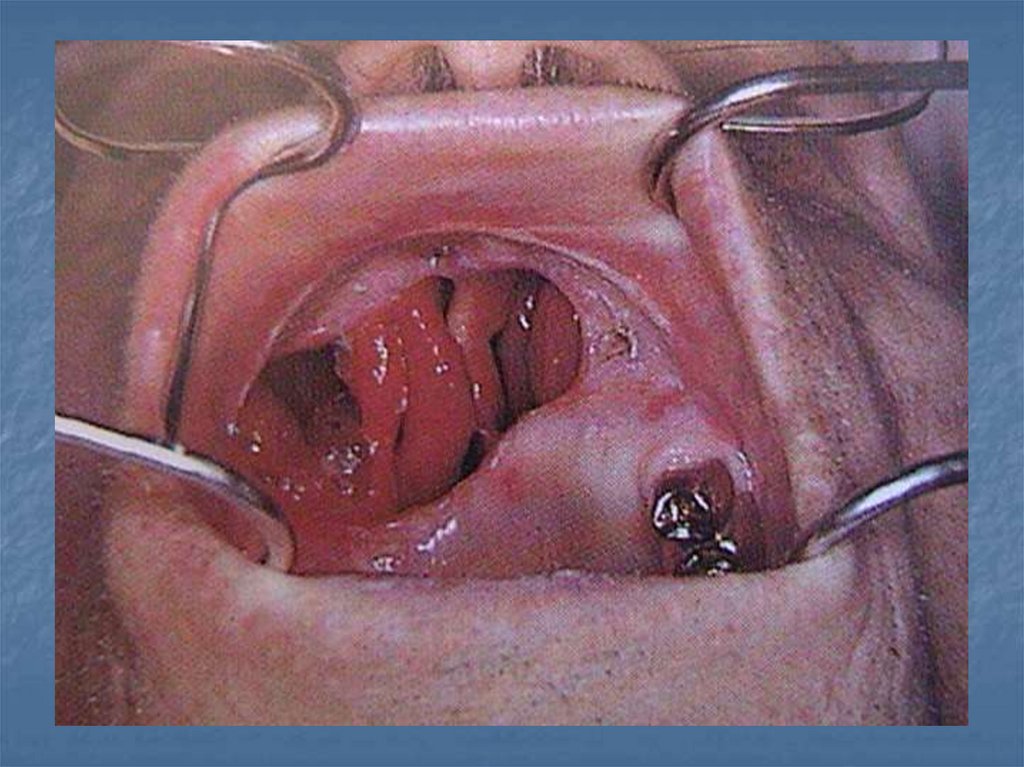

53. Tedavi obtüratörleri

Ameliyatı takip eden ilk hafta da ölçü

alınarak hazırlanan protezlerdir. İyileşme

henüz tamamlanmamıştır. Ölçü esnasında

ve protezin kullanımı esnasında mevcut

yaraların tahriş ve enfekte olmaması için

protezin sınırları kısa tutulur.

8-12 hafta kullanılır.